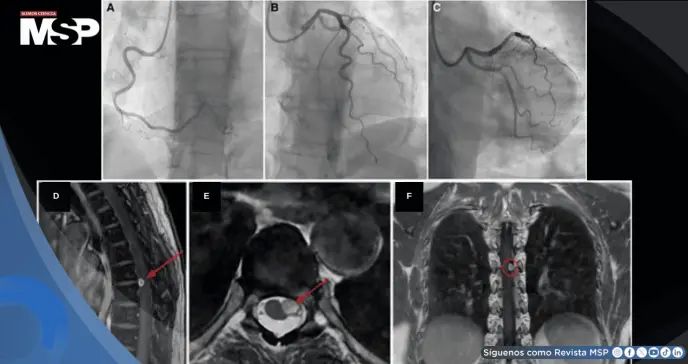

La angiografía coronaria invasiva (ICA) confirmó la ausencia de enfermedad arterial coronaria obstructiva (estenosis <50%), clasificándola dentro del espectro de angina sin arterias coronarias obstructivas (ANOCA).

Dada la persistencia de los síntomas, se realizó una evaluación funcional coronaria (CFT) mediante infusiones intracoronarias de adenosina y acetilcolina, con resultados normales:

FFR: 0,94

CFR: 3,0

IMR: 7

Durante la prueba, la paciente refirió dolor torácico sin evidencia de vasoespasmo epicárdico ni microvascular, lo que fue compatible con un posible síndrome cardíaco sensible.

Una resonancia magnética de columna vertebral reveló una lesión expansiva intradural extramedular lateral izquierda a nivel D6-D7, compatible con un schwannoma espinal.